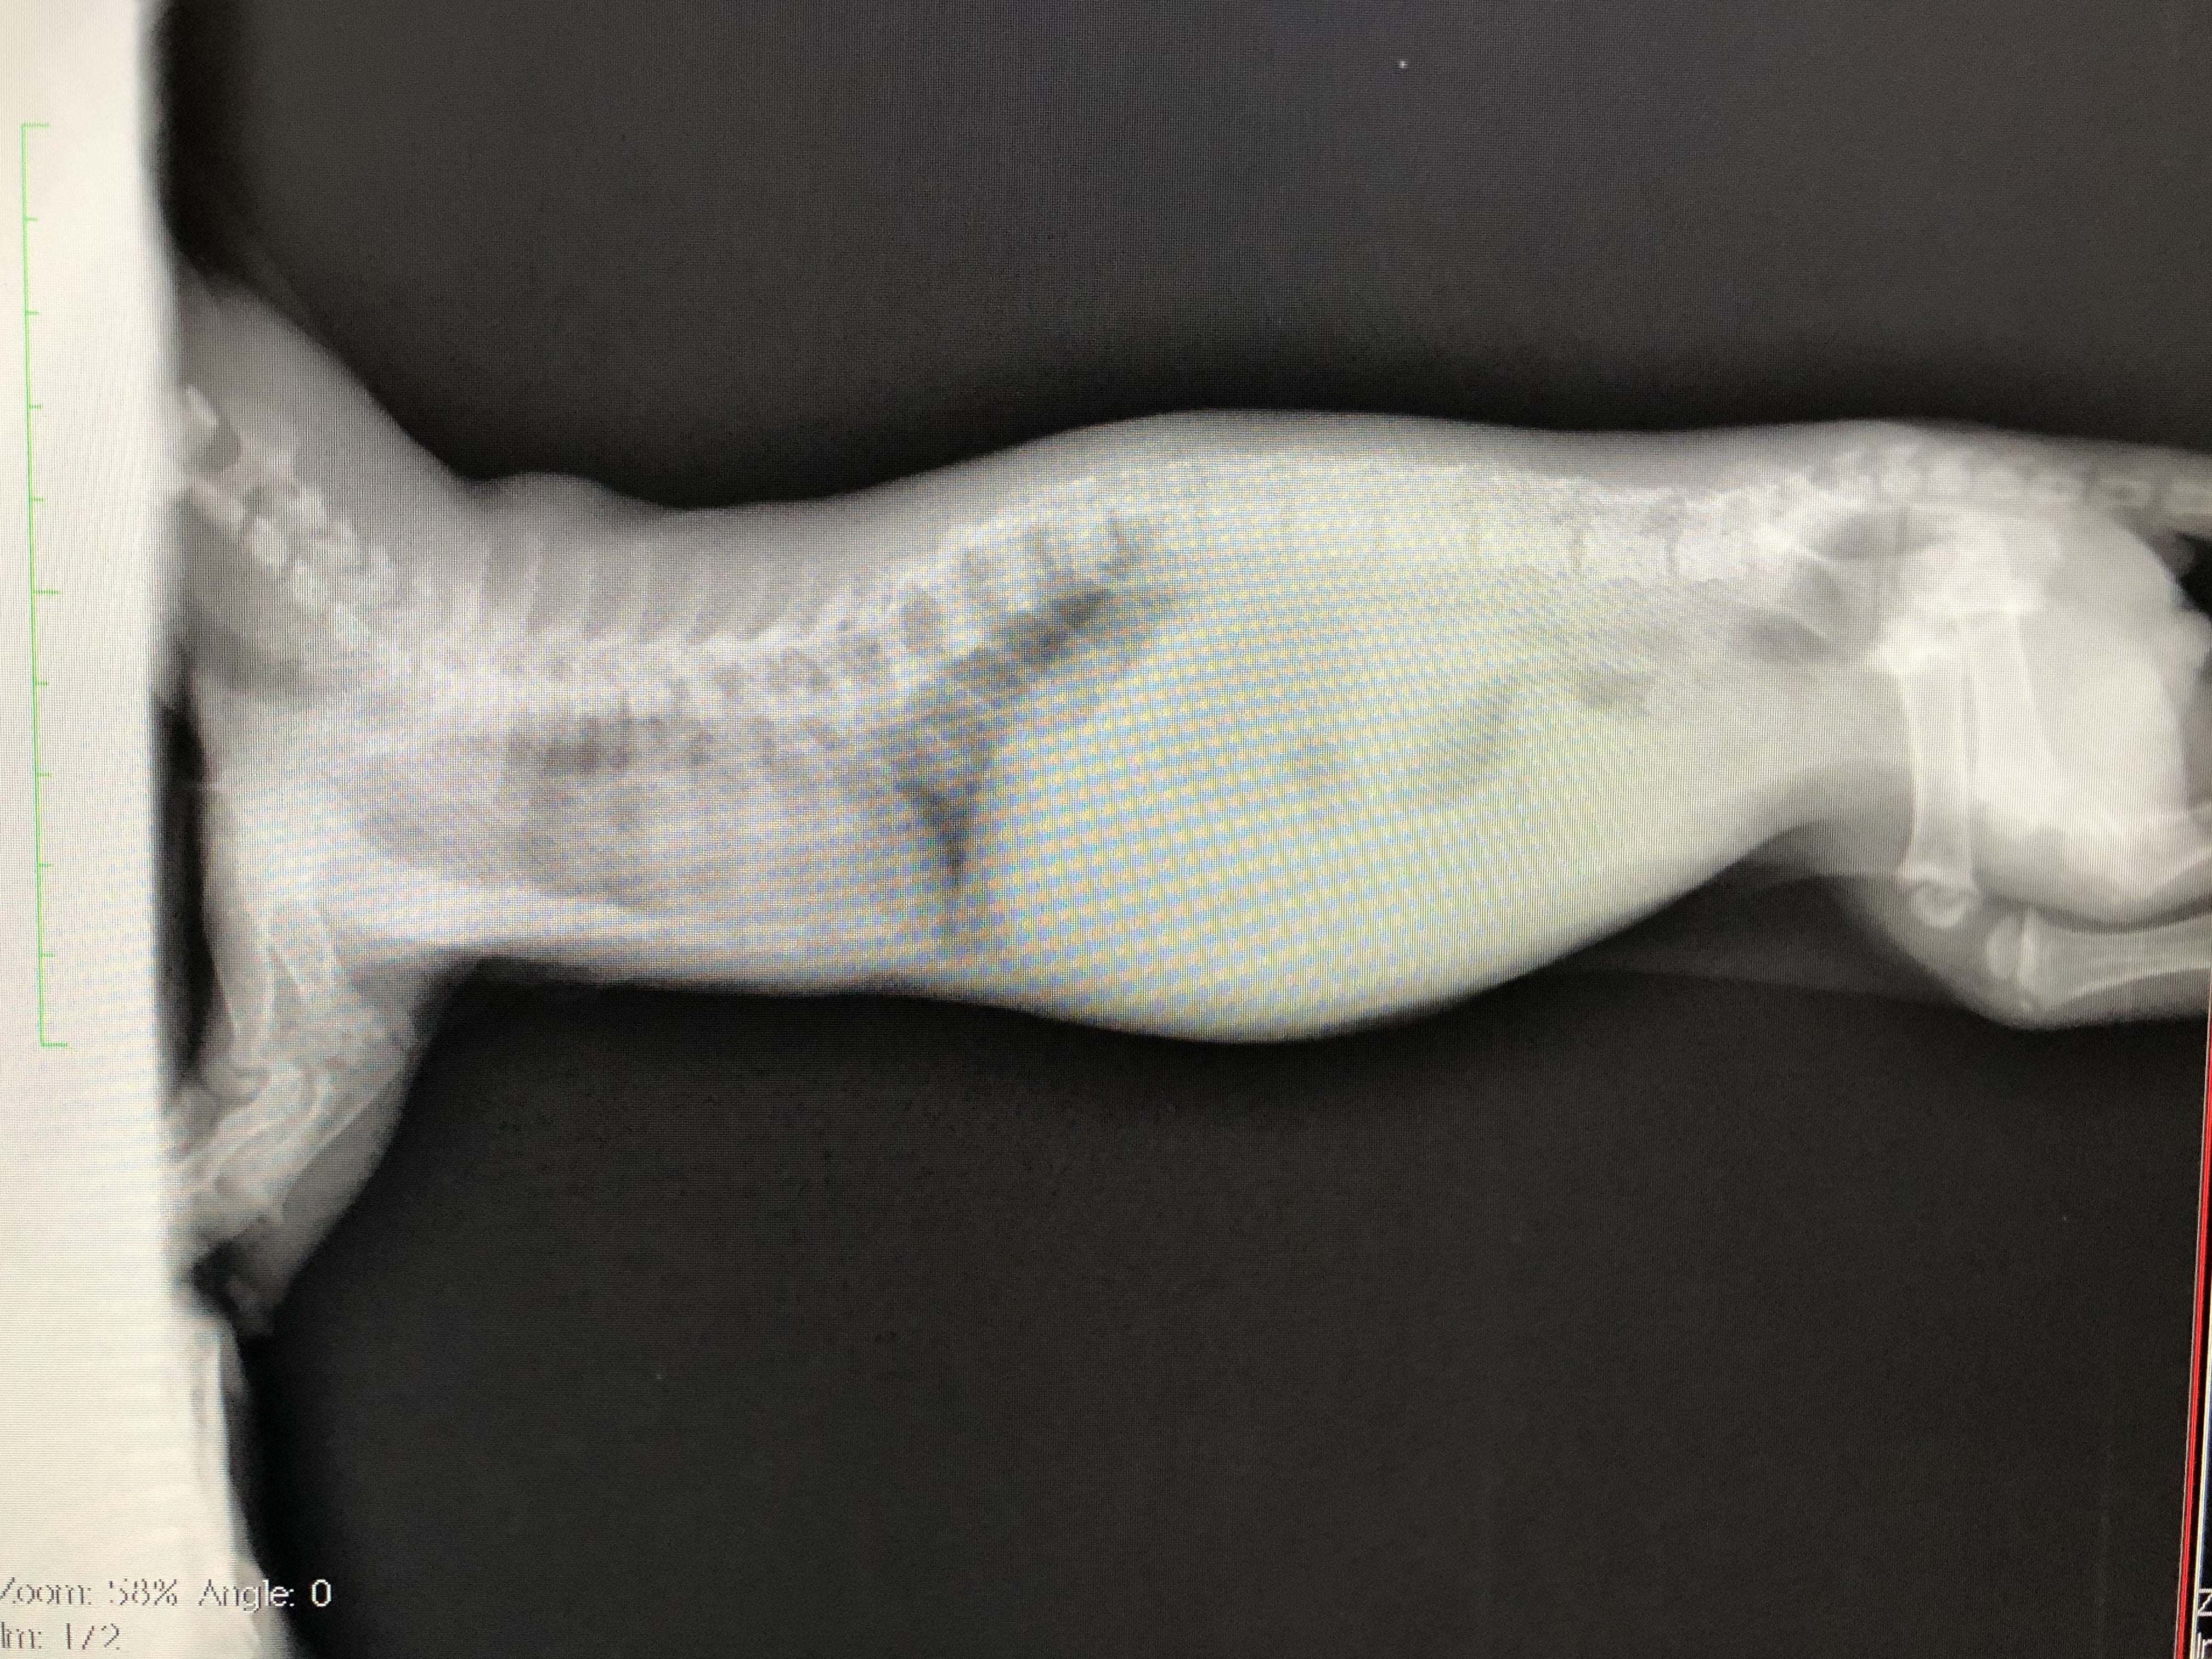

肋骨変形に伴う脊椎側変症

先天的な骨格異常で背骨と肋骨が変形していると診断されました。

また、この骨格異常により、肋骨と背骨の間のスペースが狭く、このまま成長していくと心臓と肺が圧迫され最悪生きられないと言われました。

よく休憩していたのは肺のスペースが狭いことによる影響で呼吸がしにくかったようです。